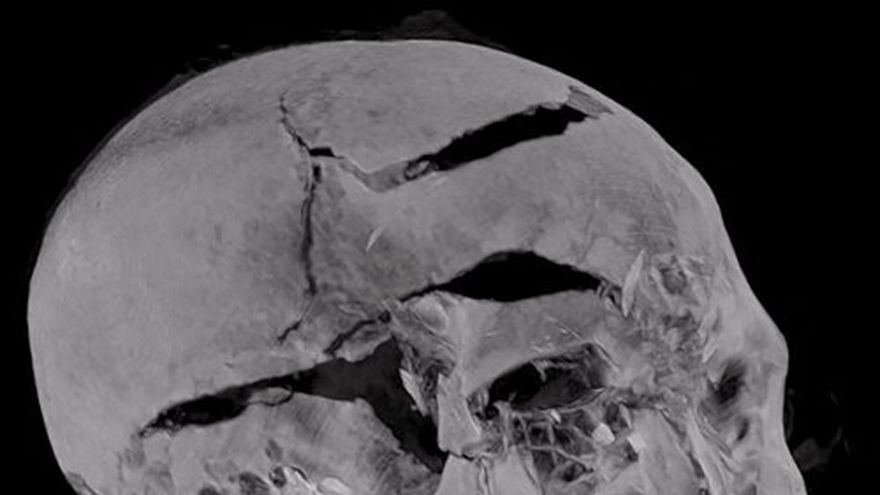

Tomografía hecha al cráneo del faraón Seqenenra Taa II

Tomografía hecha al cráneo del faraón Seqenenra Taa II / AFP

Apoyándose sobre todo en imágenes tridimensionales, el estudio realizado a la momia por el arqueólogo Zahi Hawass y el profesor en radiología de la universidad de El Cairo, Sahar Salim, sugiere que el faraón murió a manos de sus enemigos en una "ceremonia de ejecución", luego de haber sido capturado en el campo de batalla, de acuerdo a un comunicado del ministerio de Antigüedades egipcio.

El análisis de las armas (hachas, lanzas y dagas) que utilizaban los hicsos determinaron su "compatibilidad con las heridas" de la momia y también se descubrieron hematomas, hasta ahora ocultos por el trabajo de los embalsamadores.